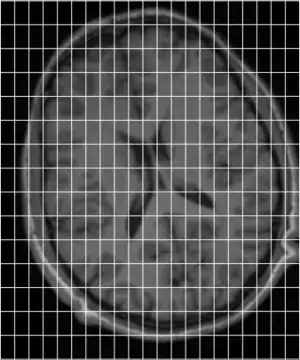

In order to get a better understanding of how mni_autoreg or indeed linear registration works, here is a simple example. Suppose we have an image of an individual and wish to align this with a model. These two images are shown below, the individuals image on the left (indiv.mnc) and model (model.mnc) on the right. Note that both of these files have different sampling and voxel sizes as illustrated by the white lines